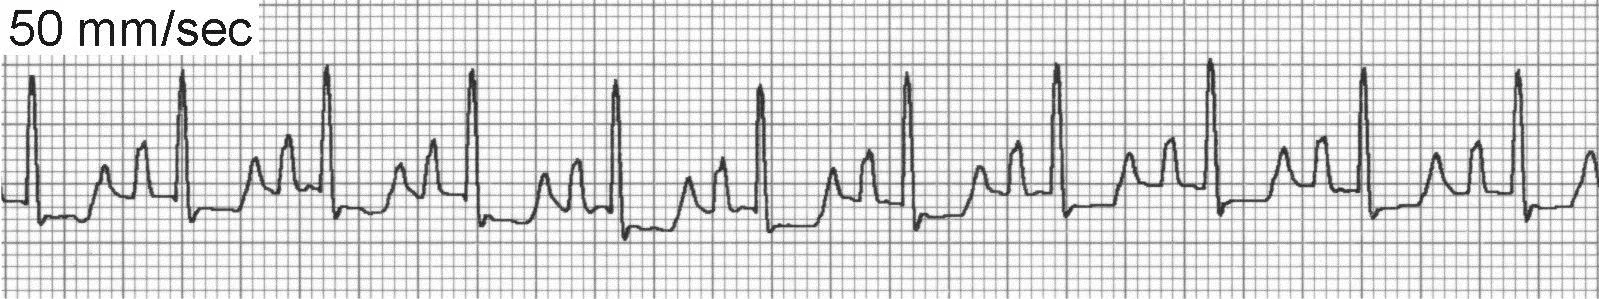

ECG of Atrial Fibrillation

The 3 ECG hallmarks of AF include absence of identifiable P waves in all leads, supraventricular QRS complexes, and an irregularly irregular rhythm. The baseline may frequently display oscillations but the organization is ill defined.